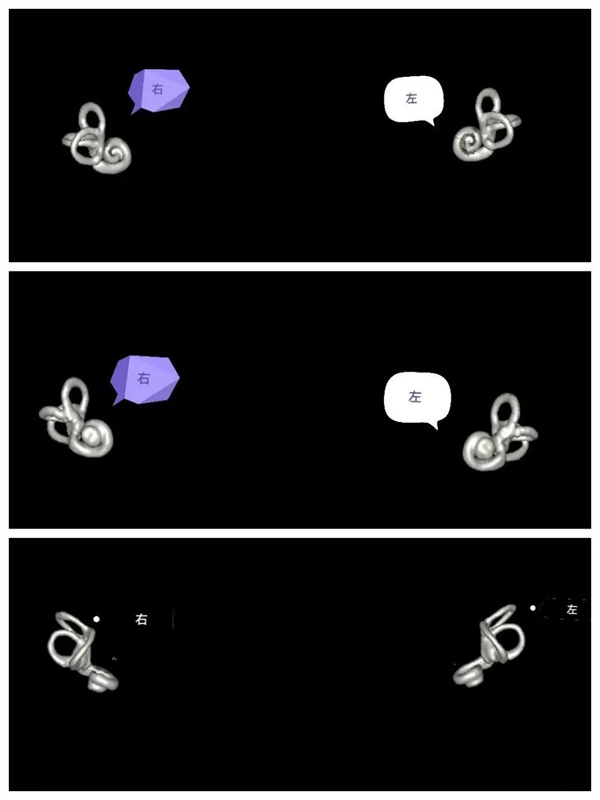

圖7:VR圖,雙側(cè)內(nèi)耳解剖輪廓圖的不同角度顯示圖(后面觀,前面觀,上面觀)。

圖8:VR圖,單側(cè)內(nèi)耳解剖輪廓前面和側(cè)面圖。